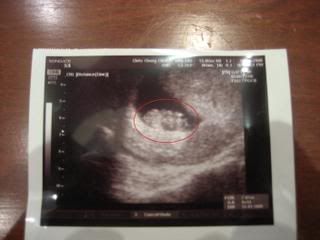

Finally we have seen our little baby Jason or little baby Ophe waving at us from an ultrasound monitor after 9 weeks of waiting! It was really amazing! Dr Chris Chong, Mummy Ophe's gynae from Gleneagles asked, "Can you see the little hands waving? Hello daddy!" And both Daddy Jason and Mummy Ophe broke into our big smiles! Then Dr Chong pointed to us our little baby head and buttocks! It was really cute. Our baby is only 9 weeks 1 day old on 11 June 2008 and a mere half thumb sized, 2.42cm...

And we were awarded with the first ever picture of our little darling-the ultrasound scan which we are so proud of! Went around showing it to our friends and family even though the picture is a little blur and we can't seem to be able to see the little one clearly on the picture!!! Now we are searching for a little nickname for our little one so that its easier to address him or her! Thinking of Thumbelina since the first time we ever met our little one, he or she is smaller than the size of daddy's thumb!

Can you see the little sweetheart circled in red? Shall do a better scan on our printer when we are back in AZ! :)